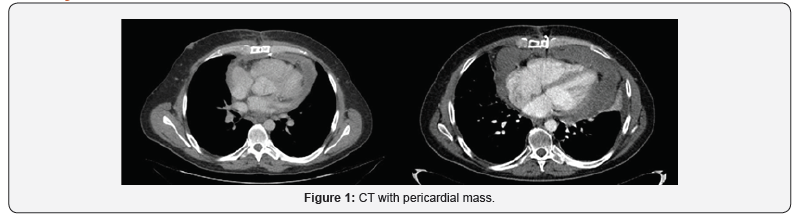

40-year-old man visited our Hospital in June 2014 due to chest pain. The physical examination had no abnormal findings. After admission, the chest X-ray indicated cardiomegaly and echocardiography showed dates of pericardial effusion. The patient received treatment and was discharged from hospital after one week with pericarditis diagnosis. Four months later, he started with similar symptoms and echocardiography showed massive pericardial effusion with a tumorous region in the pericardial space. Echocardiography showed a big mass with compression of right cavities without stenosis, gradient valve tricuspid of 3,7mmHg. The chest CT, as well as confirming the effusion, revealed a pericardial cystic mass with pericardial thickening (Figure 1). Is suggested of neoplasm like mesothelioma or sarcoma. Pericardiocentesis was performed and 1000 mL of mpericardial fluid was drained. According to these findings, surgical resection through pericardiectomy with median sternotomy was performed on October 2014 with pathology study. The tumor was in the pericardial space, with irregular morphology, size of 14×5.7x6 cm and 1500mL serohematic pericardial fluid. Histological analysis showed spindle cells-type sarcoma, necrosis and 18 mytosis. Immunohistochemical analysis showed that the tumor cells were positive for bcl-2, CD99, vimentin and the Ki-67 proliferative index was 50%; however, staining for S100 proteins, CD34, CK AE1/AE3, EMA, enolasa, musclespecific actin (HHF35) and desmin was negative. On the other hand, fluorescence in situ hybridization revealed a moderate prevalence (64%) of cells with interruption of the SYT gene (18q11.2). Final diagnosis was monophasic synovial sarcoma with poorly differentiated areas with unspecified margins. Patient had a good clinical evolution but the control CT scan three months later, showed tumor persistence, 7.5x11x2.8cm with compression in right ventricle. The tumor grew from the inner surface of the pericardium near the origin of the pulmonary artery and ascending aorta with invasion of left atrium and right coronary. The study was completed with angiography scan. The case was evaluated in multidisciplinary committee. The specialist decided re-intervention, but complete resection was not possible because of the proximity and attachment to the great vessels. In CT scan after surgery, the mass was reduced around 50%. In multidisciplinary committee, we discussed the possibility of adjuvant radiation therapy. Finally, patient received radiation treatment with prescription dose of 45Gy, 1.8Gy daily (Figure 2). He didn´t had any toxicity. After three months, patient had a new recurrence. In committee we decided not surgery, patient received chemotherapy. Finally, patient had a new recurrence and died in 12 months after diagnosis (Figure 3).